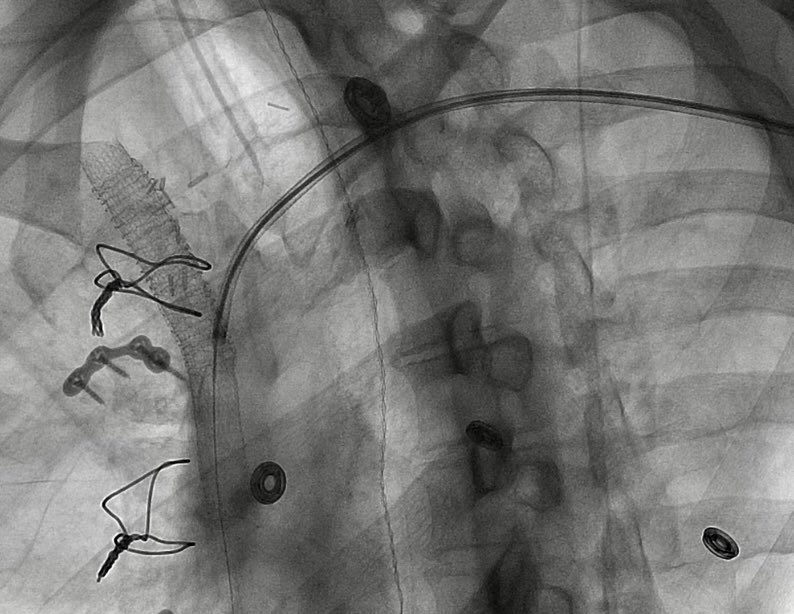

.@LucasRCmd, MPH; @HiroSparks, MD; Kara E. Masterson, MSN, NP; Scott J. Genshaft, MD; @AdamPlotnik, MD; and Siddharth A. Padia, MD, contributed to this open access article. See what they've been working on! brnw.ch/21wPx6v